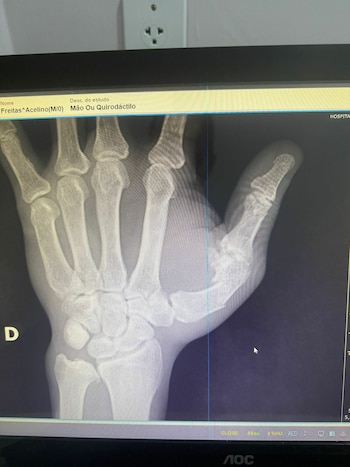

El propio Freitas padre también resultó herido en la trifulca y debió someterse a una cirugía por una fractura diafisaria del primer metacarpiano en la mano derecha. La oficina de prensa del boxeador confirmó a Globo el procedimiento realizado en Salvador y detalló que las tomografías practicadas descartaron lesiones en el cráneo, aunque permanece bajo monitoreo médico.